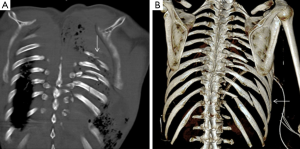

A nondisplaced rib fracture is defined as a rib fracture with complete cortical disruption but with maintained alignment, usually involving the medullar bone and both the inner and outer cortices (Figure 1); it is seen such a lucent line on radiographs or CT images (14). Stress rib fractures are overuse injuries that occur when there is an abnormal force on normal underlying bone. These begin with a small stress on the bone, which with repeat injury results in a microtrabecular fracture that may progress to rib fracture. These injuries are rare, although possibly underdiagnosed, and most often seen in workers who perform repetitive motions and athletes. Detection of non-displaced and stress rib fractures on radiographs is difficult, and these injuries may be seen radiographically only at follow-up imaging, after signs of healing have manifested (7). On the contrary, MRI can show immediately an area of oedema (high T2 signal) after a traumatic event. When cortical disruption and a substantial abnormality in alignment are evident, a rib fracture is classified as displaced. Displacement may be minimal or obvious. Displaced fractures may be identified on radiographs or CT images (Figure 1). Injury to the surrounding tissues and structures can occur, and several lethal complications such an aortic injury have been documented in the literature (15). A buckle fracture of the rib occurs when there is disruption of either the inner or outer cortex (Figure 2) with no observable fracture of the other cortex (16). Some researchers have reported that the term buckle is derived from engineering terminology that describes disruption of the inner or tensile side of a structure that is placed under force (7,17). Flail chest (“volet”) is a traumatic condition in which there are three or more contiguous ribs with fractures in two or more places (Figure 3). Fractures usually occur in the anterior and anterolateral portions of the middle to lower ribs (1). These fractures create a flail segment that can move paradoxically relative to the remainder of the chest during respiration in a spontaneously ventilating patient. Although imaging can show fractures, it is the clinical examination that will demonstrate paradoxical motion. Flail chest serves as a marker for significant intrathoracic injury, since more than one-half of the affected patients may have associated injuries that require surgical treatment (18).

Injury to the rib-cartilage complex can occur at multiple sites along the anatomic arc from spine to sternum. Injuries to the chondrocostal junction (Figure 4) are termed rib separations, while nearby disruptions of the chondrosternal junction are called rib disruptions. The cartilage may itself be fractured (19). Radiographs, although useful for detecting osseous abnormalities, are insensitive to detect cartilage and soft-tissue abnormalities. Because costal cartilage injuries are often located in the junctional regions; chondrosternal and chondrocostal, the overlapping osseous structures in these areas limit the usefulness of radiographs. A Canadian study from Subhas et al. showed that cross-sectional techniques such as CT, US and MRI are more sensitive to detect these injuries (Figure 5) (20). On CT, cartilage density is relatively uniform (70–120 HU), in which this value is higher than fat and muscle but lower than calcium (Figure 6). Costal cartilage fractures are visualized as a low-density area through the costal cartilage, with surrounding calcifications near old fractures and gas density within the cleft in some cases. Swelling of surrounding soft tissue could also be seen. Other imaging techniques such as MDCT, US and MRI have been evaluated. In the largest published series, Malghem et al. described a series of eight patients with 15 costal cartilage injuries diagnosed on CT in all patients and on US in three of them. Their patient population was young (mean age, 27.5 years), and all of them had a prior traumatic injury, related to contact sports in three patients (19). Costal cartilage injuries are readily visible on MRI because of the high signal from the surrounding oedema; they are often more conspicuous than those of CT images. Even in cases of remote injury, high T2 signal was visualized at the site of fracture that was presumably due to non-union given the persistent clinical symptoms. In fact, the characteristically imaging appearance of MRI for cartilage injuries, as in ribs fractures, is an increase oedema-like signal on T2 at the site of injury. Also, oedema-like signal T2 could be seen in the surrounding soft tissue in recent or subacute injuries (<3 months). A fracture line, which is not always present, appears as a localized linear oedema-like decreased T1 and increased T2 signal, and it is best to be visualized on the fluid-sensitive sequences (fat-saturated fast spin-echo T2-weighted or STIR-weighted sequences) and in the coronal plane (20).